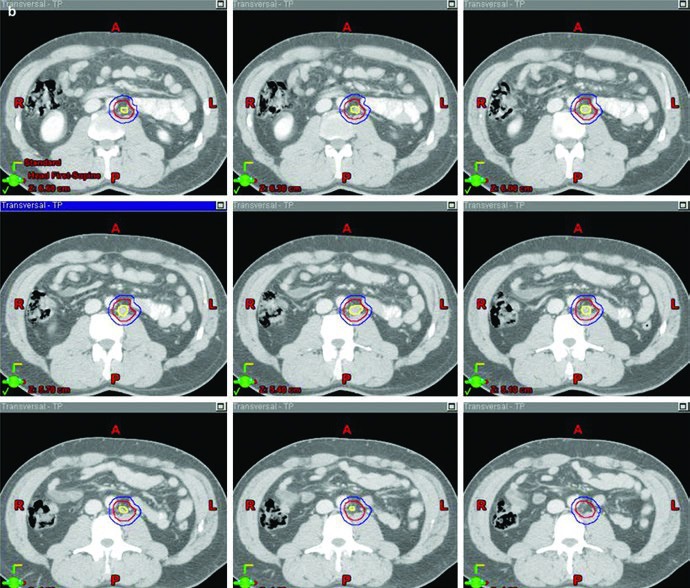

No estágio II, a resposta do capítulo muda de escala. Aqui, os pacientes com seminoma puro podem ser tratados com um campo dogleg, com dose total de 30 Gy para estágio IIA e 36 Gy para estágio IIB. Como alternativa, o texto cita quimioterapia primária, tipicamente com etoposídeo e cisplatina, com ou sem bleomicina, por 3 a 4 ciclos. Mais uma vez, o livro organiza radioterapia como uma opção sólida, mas não como único caminho possível.

O ponto técnico mais útil é que o dogleg não nasce do zero. Ele começa com o mesmo contorno de cava inferior e aorta usado no estágio I e, em seguida, incorpora vasos ilíacos comuns, porções proximais dos ilíacos internos até a emergência da glútea superior e vasos ilíacos externos até a borda superior do acetábulo, com expansão de 1,2 cm respeitando limites anatômicos. Depois disso, o capítulo pede contorno da doença nodal grosseira, o GTV, com expansão de 0,8 cm respeitando a anatomia, formando um CTV nodal. A união do CTV vascular com o CTV nodal produz o CTV inicial.

Esse campo inicial recebe expansão de 0,5 cm mais 0,7 cm até a borda do bloco para compor o PTV inicial, ainda na faixa de 20 a 25,5 Gy com frações de 1,5 a 2,0 Gy. O boost em conedown segue a mesma lógica geométrica aplicada ao CTV nodal, também com 0,5 cm mais 0,7 cm até a borda do bloco, até completar 30 a 36 Gy em 2 Gy por fração. O capítulo ainda acrescenta uma regra simples e prática para a doença visível: garantir margem de 2 cm ao redor de toda adenopatia grosseira visível.

Os marcos anatômicos ajudam a não perder o eixo do campo. Superiormente, o limite permanece no topo de T11, com a mesma nota de que algumas fontes usam topo de T12. Inferiormente, o capítulo posiciona o limite no topo do acetábulo, embora algumas fontes recomendem o meio ou a base do forame obturatório. A borda lateral acompanha as pontas dos processos transversos das vértebras lombares, tipicamente em torno de L3, considerando a posição dos rins, e se estende inferiormente para cobrir a borda lateral do acetábulo. Para seminoma à esquerda, a cobertura do hilo renal esquerdo volta a aparecer como opcional.

A figura de boost fecha esse raciocínio muito bem. Ela mostra, em um exemplo de estágio IIA, a diferença entre GTV em amarelo, CTV em vermelho e PTV em azul. Não é só uma ilustração bonita; é a prova visual de que o capítulo separa volume eletivo, volume inicial e volume de reforço com precisão suficiente para orientar planejamento real.

Simulação, imobilização e entrega do tratamento

O capítulo fecha com instruções de simulação que merecem ser lidas como parte do delineamento, não como detalhe operacional separado. Na instituição dos autores, os parâmetros-padrão incluem tomografia com espessura de corte de 2 mm, paciente em decúbito dorsal e braços elevados. A imobilização é feita com alpha cradle. Para pacientes em estágio II, contraste intravenoso é usado com frequência para ajudar no delineamento da doença nodal grosseira. Se o paciente já tiver PET de estadiamento, esse exame também pode ser fusionado com a tomografia de simulação.

Outro cuidado explícito do capítulo é a proteção do testículo contralateral íntegro com um clamshell. Esse detalhe reforça o tom geral do texto: mesmo em uma doença altamente radiossensível, o planejamento não dispensa disciplina técnica. A mesma lógica aparece quando os autores afirmam que a abordagem padrão de tratamento para seminoma é 3D-CRT com campos AP/PA, definidos por marcos ósseos ou pela anatomia vascular. Não há promessa de sofisticação vazia aqui. Há uma técnica conformacional clássica, bem especificada e sustentada pela cartografia nodal.